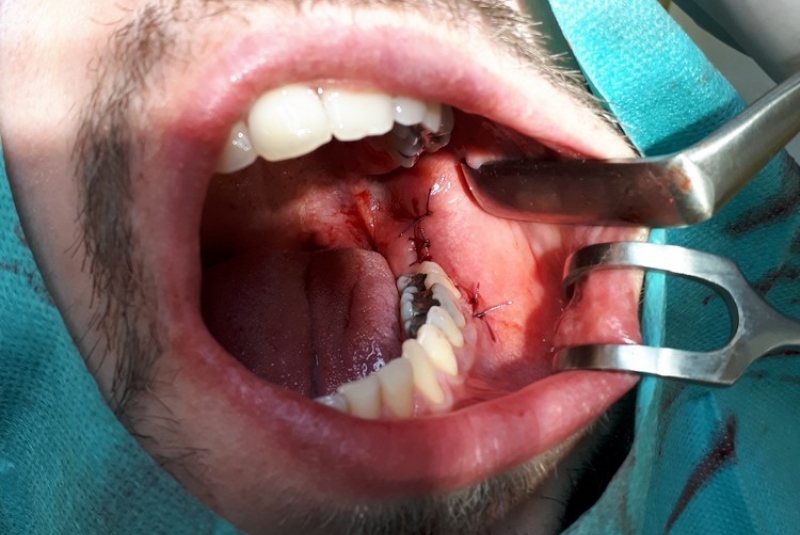

- Resekcia (odstránenie zápalového ložiska zubného pôvodu)

- Chirurgické extrakcie

- Chirurgia detí a dorastu